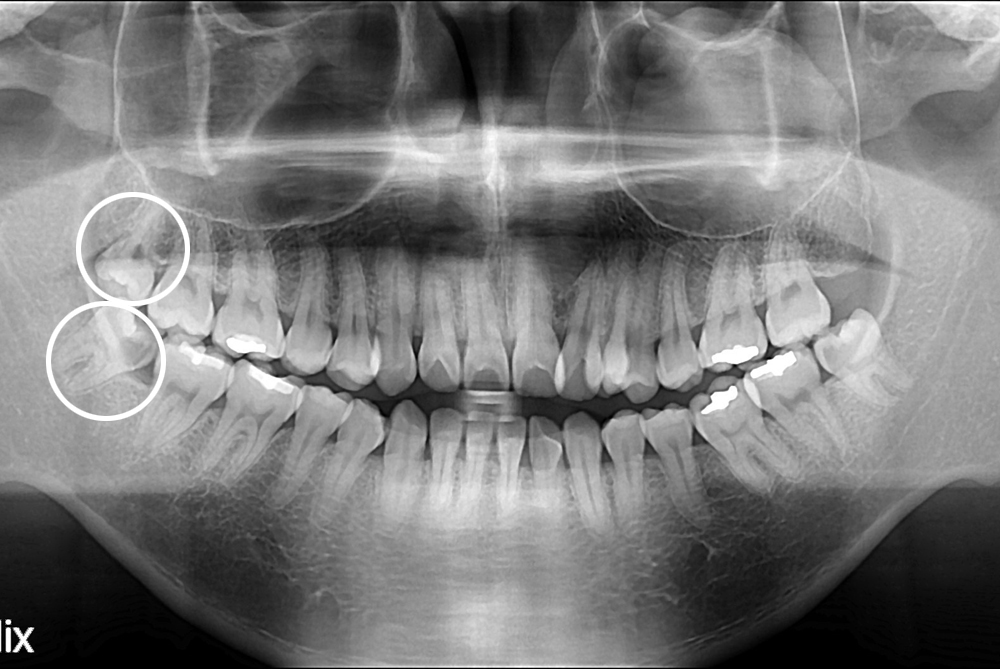

[사랑니] 난발치 사랑니 발치

치료후 : 2017-06-23

세종치과는 구강악안면외과학 박사이신 원장님이 발치하는 치과입니다.